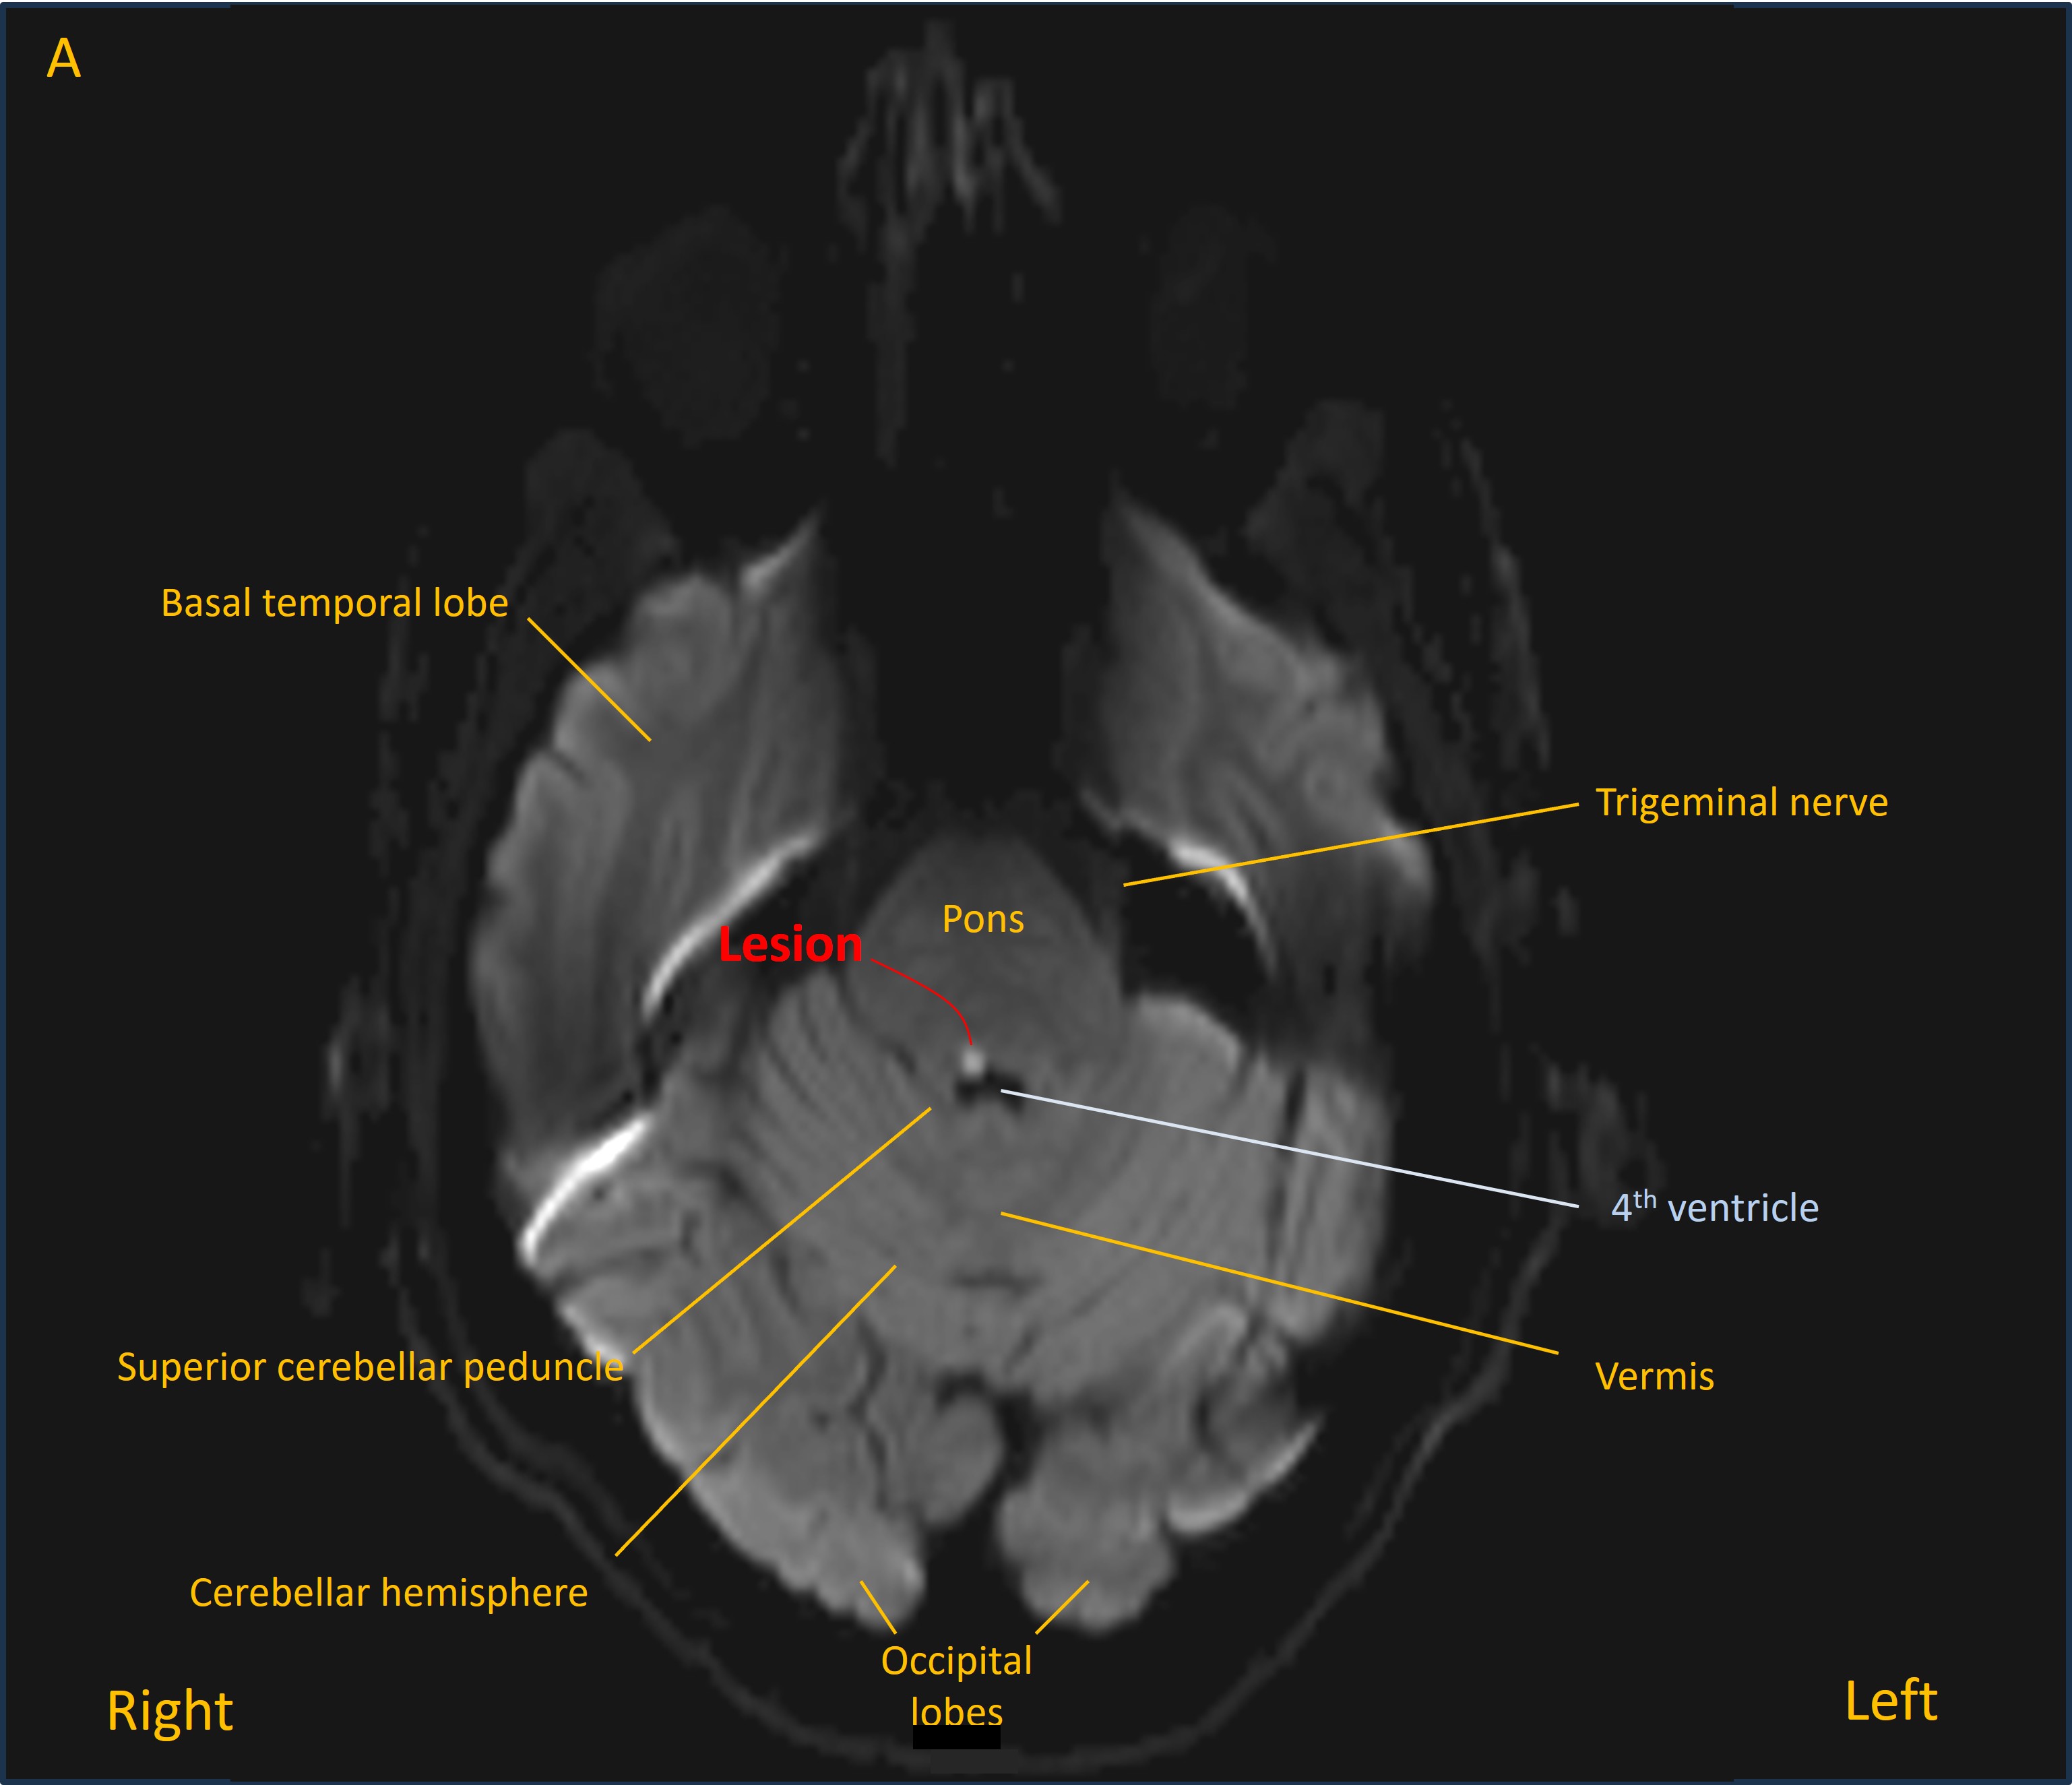

A CT head was unremarkable, but has low sensitivity for many lesions in the posterior fossa, so an MRI was performed. This showed an acute lacunar infarction in the right dorsal upper pontine tegmentum - bright on diffusion-weighted imaging (image A) and dark on apparent diffusion coefficient map (image B).

MRI B